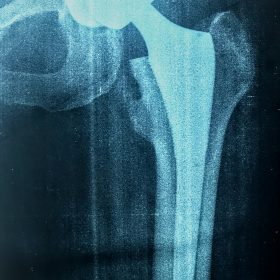

Διάγνωση- Σταδιοποίηση

Διακρίνονται σε 4 στάδια.

Στάδιο Ι. Στένωση του μεσαθριου διαστήματος

Στάδιο ΙΙ. Σκλήρυνση του υποκύμενου χόνδρου

Στάδιο ΙΙΙ. Σκλήρυνση του υπερκείμενου χόνδρου, καταστροφή του υποχόνδρινου οστούν, σχηματισμός οστεόφυτων, οίδημα αρθρώσεως και βραδυνός πόνος

Στάδιο IV. Οστική καθίζηση, καταστροφή μαλακών μορίων μυϊκών ομάδων, υπεξάρθρημα της αρθρώσεως και αλλαγή του μηχανικού άξονα